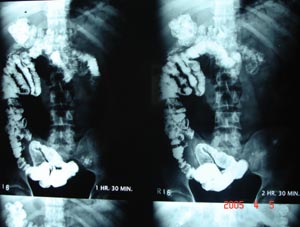

Barium x ray

Transverse folds of mucous membrane project into the lumen of the bowel & barium lies between the folds which appea as lucent filling defect of about 2-3 mm in width.